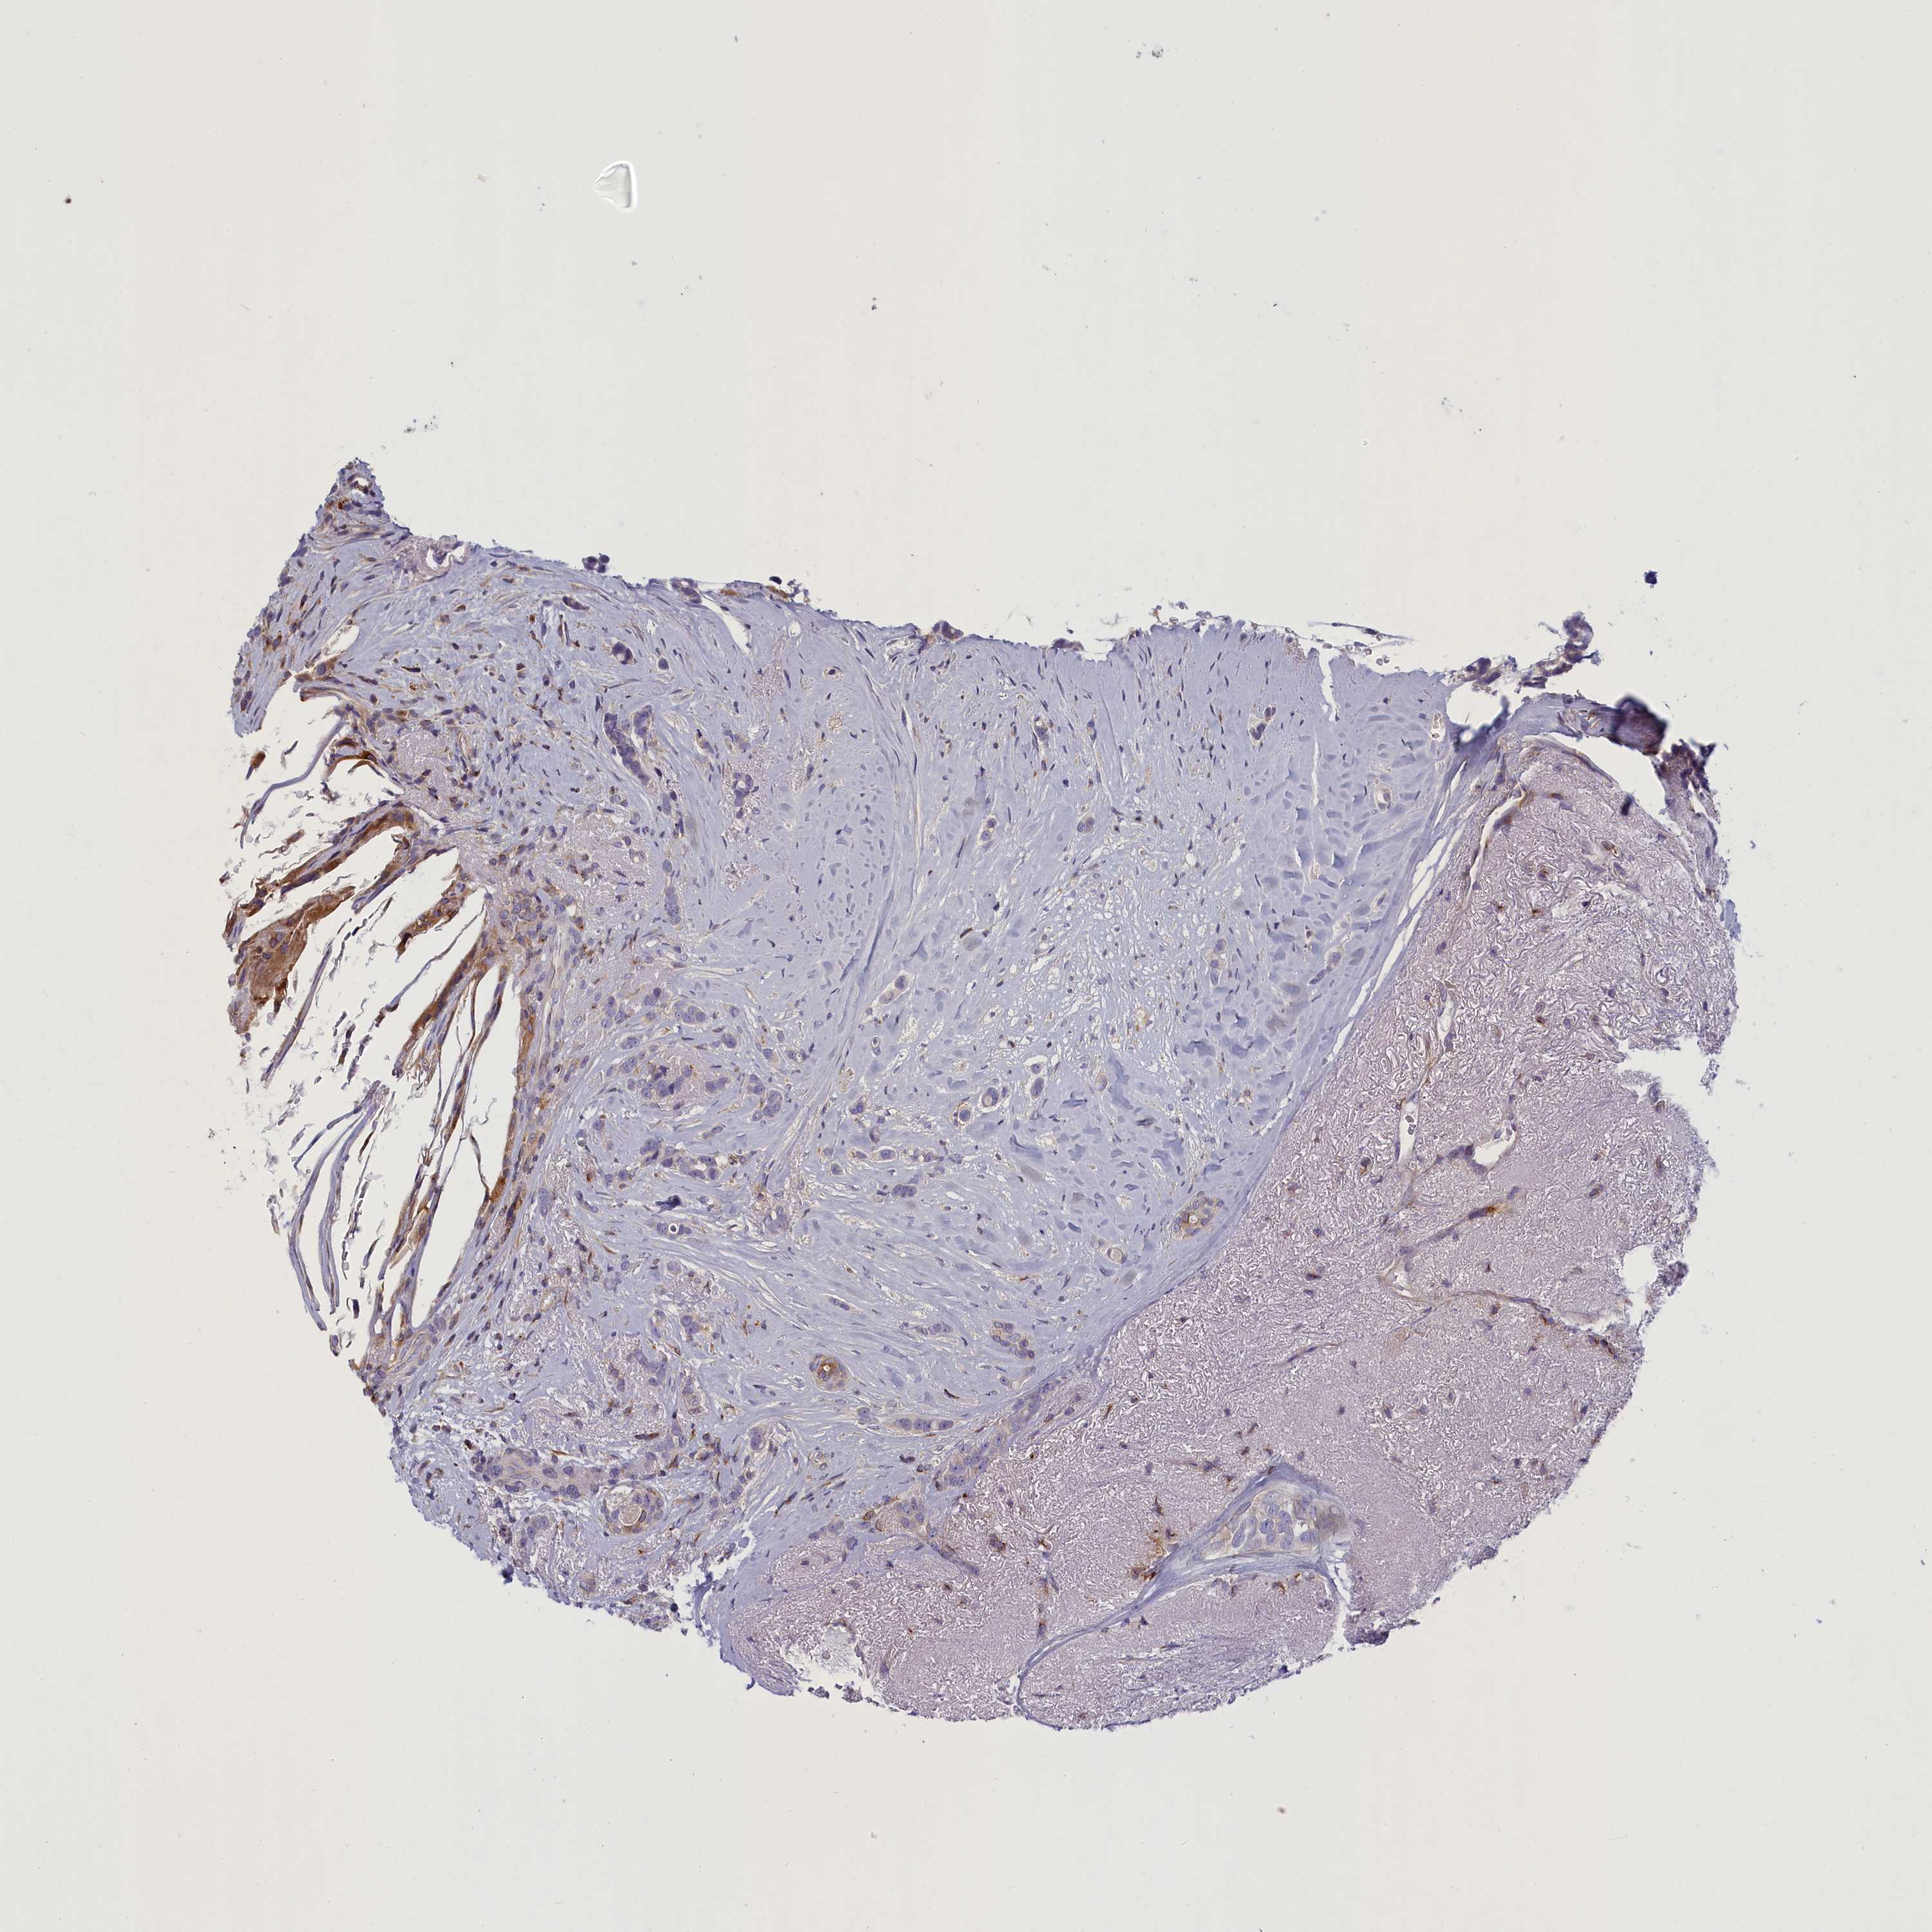

CANCER BREAST CANCER Show tissue menu

BRCA TCGA BRCA VALIDATION PROTEIN EXPRESSION

ANTIBODIES

AND

VALIDATION